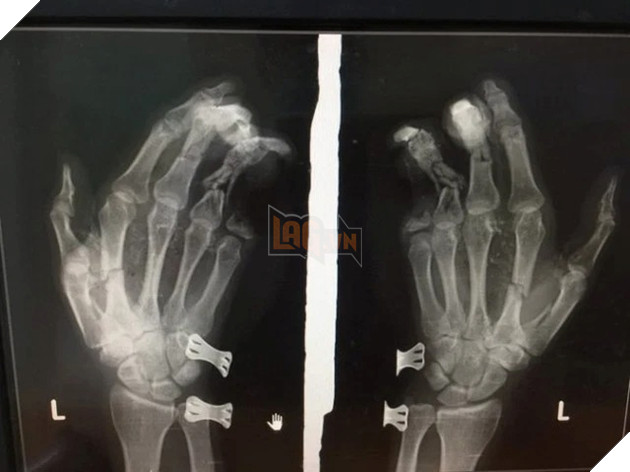

Trong những ngày của cuối năm 2021 và đầu năm 2022 đã xảy ra rất nhiều những tai nạn thương tâm liên quan đến việc sử dụng điện thoại di động. Đầu tiên đó là câu chuyện của một bé trai tại Hà Tĩnh trong tình trạng bàn tay bị dập nát do nổ điện thoại, theo như bác sĩ chuẩn đoán thì tình trạng bàn tay của bệnh nhân là vô cùng nặng nề. Được biết bé trai này vừa chơi điện thoại mà vừa sạc pin để rồi dẫn đến tai nạn thương tâm kể trên.